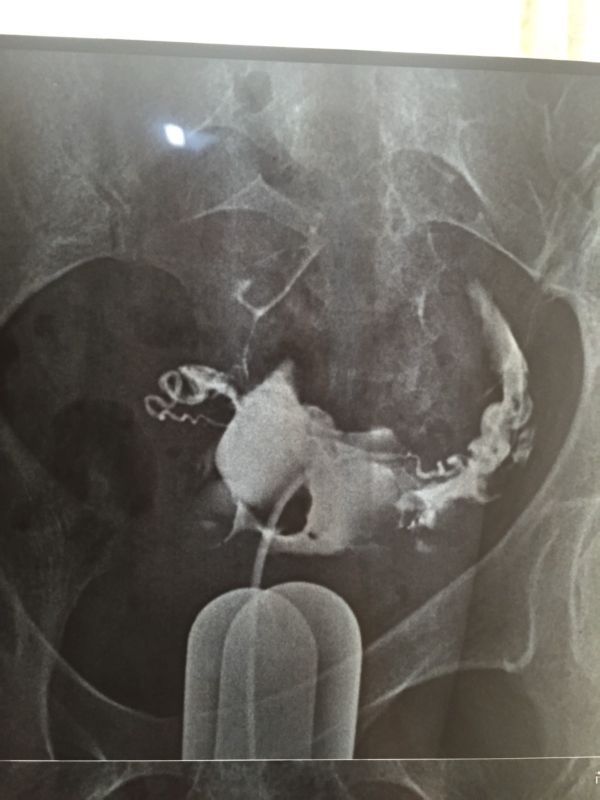

原发性不孕,碘海醇造影,双侧输卵管显示迂曲,伞端见造影剂聚积,造影剂通过双侧输卵管进入盆腔弥散,部 分呈团状显示,考虑:双侧输卵管伞端粘连,不全阻塞,请问要做手术吗?手术成功率高吗?怀孕几率高吗?急盼答复 点击展开 匿名用户 2015-03-29 18:16 为您推荐: 其他回答 你好,如果双侧输卵管不是完全堵塞的话,做手术后怀孕的几率非常大。建议你选择手术治疗,如果害怕手术失败可以选择做试管婴儿。 天使7737 2015-03-29 22:28 相关问题 右侧输卵管部分峡部显影 左侧输卵管走行迂曲,造影剂流速正常,数秒钟后可见中量造影剂弥散入盆腔,涂布 右侧输卵管部分峡部显影 左侧输卵管走行迂曲,造影剂流速正常,数秒钟后可见中量造影剂弥散入盆腔,涂布 右侧输卵管部分峡部显影 左侧输卵管走行迂曲,造影剂流速正常,数秒后可见中量造影剂弥散入盆腔,涂布欠